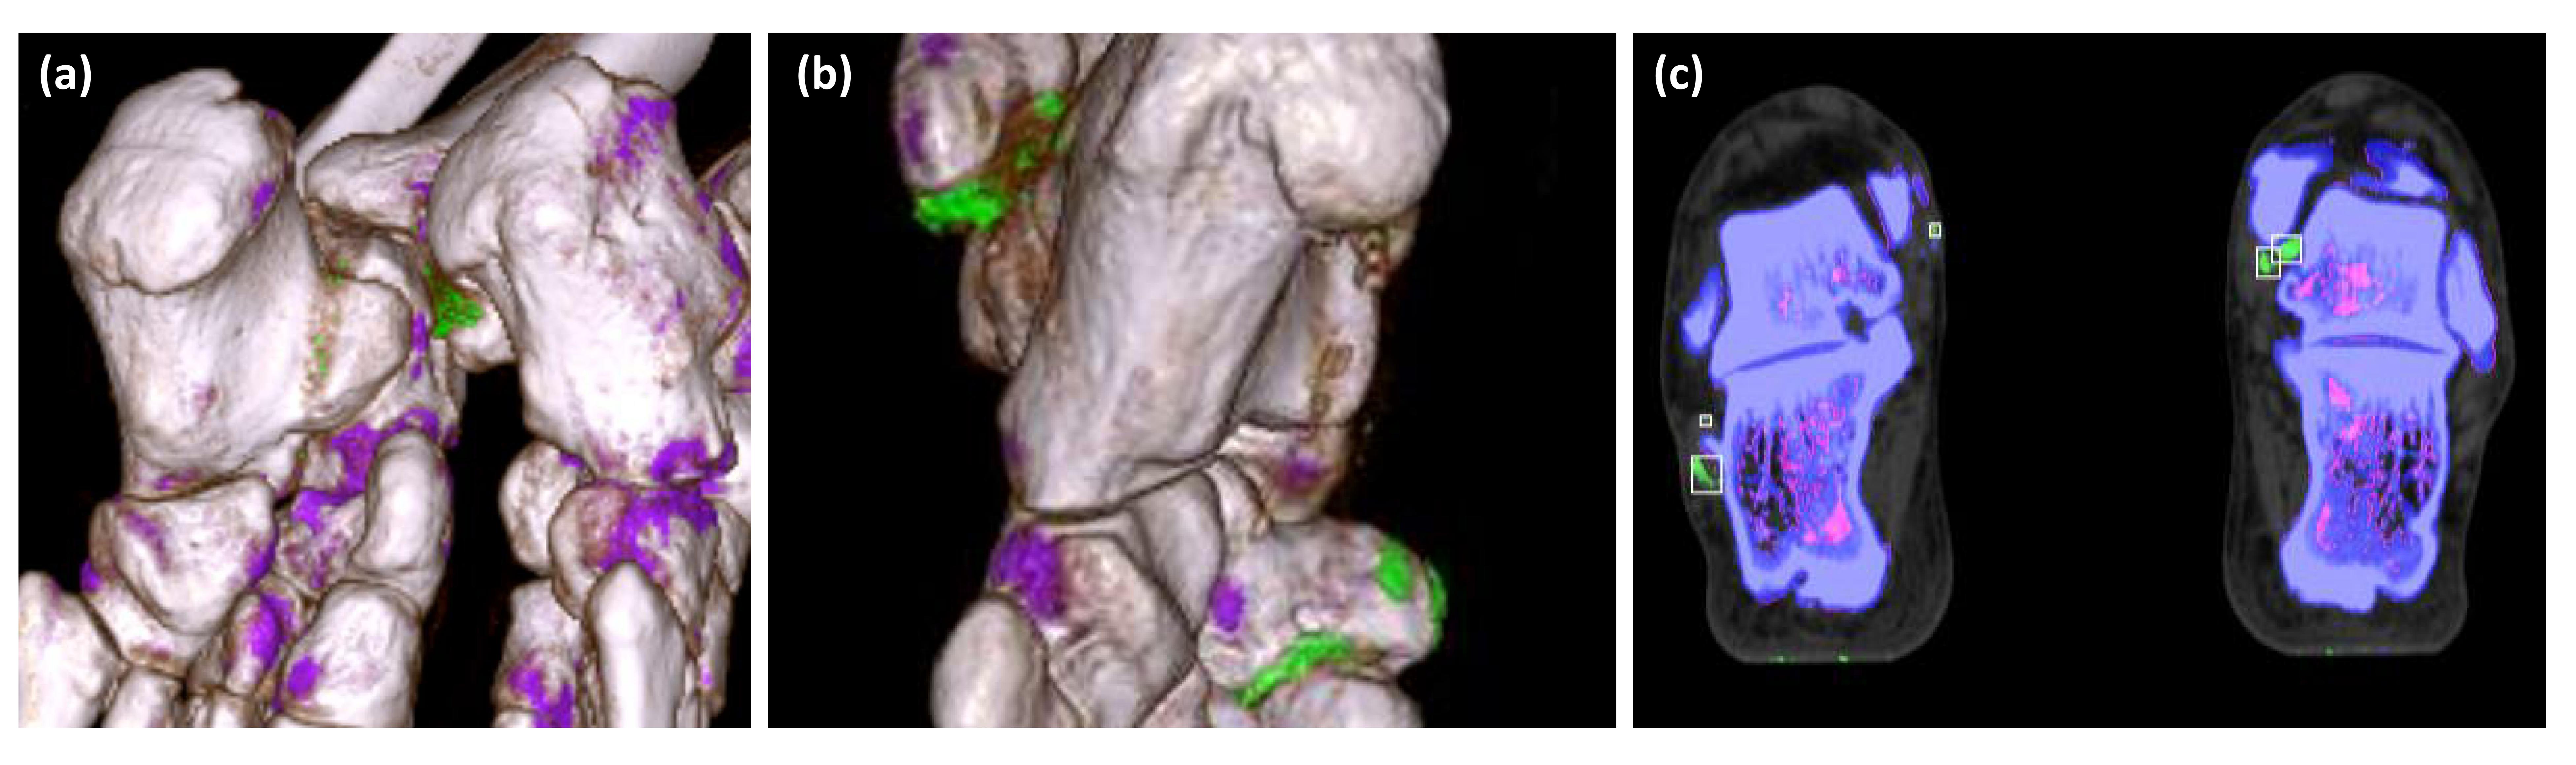

Figure 1. Applying deep learning to distinguish pseudo lesion and true monosodium urate (MSU) deposit. (a) In 3D DECT, there are pseudo lesions that appear as scattered green color foci at the hindfoot. Note that this patient obtains CT for fracture evaluation. (b) 3D DECT from gouty patients shows multiple patches of green color foci at the mid and hind foot. The green color from (a) and (b) are difficult to distinguish. (c) Final ROI labeling for deep learning.